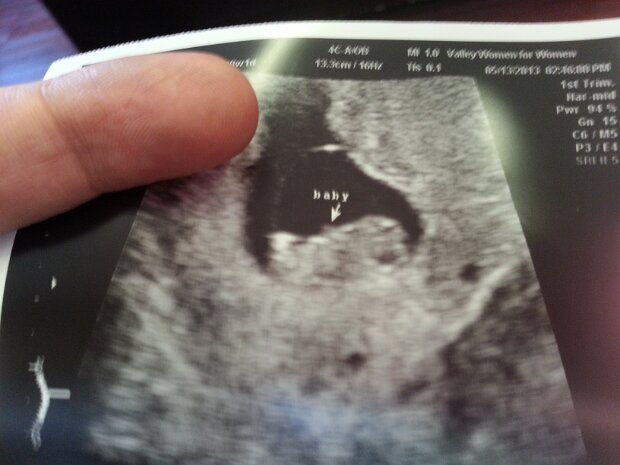

I'm Going To Be A Dad